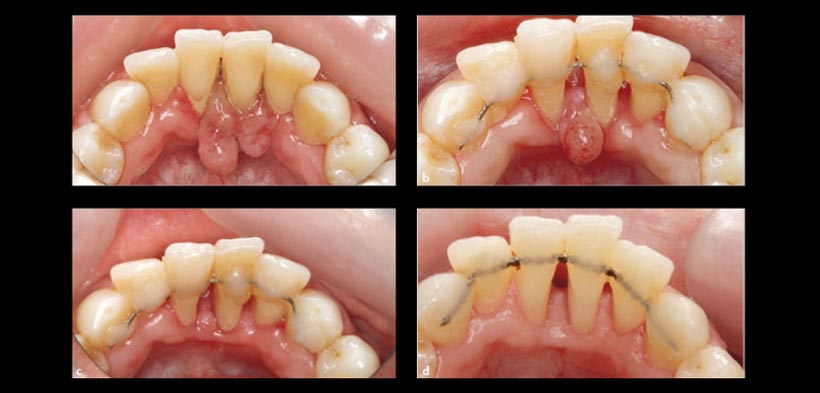

Actualmente aparecieron nuevos enfoques de tratamiento, dado que el granuloma piógeno gingival es en realidad una lesión inflamatoria que es altamente vascularizada, un tratamiento basado en  protocolos de control de placa y medicación podría tener un efecto beneficioso en la desaparición de esta lesión. En primer lugar se usa el  protocolo de control estricto de placa (hasta llegar a un valor menor al 15%) cada dos semanas. Luego se pasa a la siguiente fase mediante el uso de  fármacos  antiinflamatorios y antibacterianas como a clorhexidina 0.05% puede ser destinado a eliminar los irritantes y bajar la infección durante las siguientes semanas, La combinación de ambos protocolos llegan a ser un tratamiento eficaz que evita la necesidad de procedimientos quirúrgicos secundarios, junto con sus posibles consecuencias (fig 1 y 2).

Fig. 1. Fases de tratamiento no quirúrgico de un paciente con granuloma piógeno gingival. (A) presentación inicial de la lesión (lesión en forma de coliflor exofítica en la encía lingual entre los incisivos centrales inferiores. (B) se realiza un control de placa estricto, que consiste en la eliminación de cálculo dental, se realiza instrucción de higiene bucal al paciente y un mes más tarde  la lesión exofítica se reduce en tamaño. Las raíces de los dientes afectados están más expuestas a la recesión de la encía circundante, que también es menos eritematosa y edematosa. (C) se introduce la terapia medicamentosa mediante el uso de clorhexidina al 0.05 % y dos meses más tarde  hay contracción sustancial de la lesión, y un eritema mínimo. (D) se sigue realizando un control estricto de placa y cuatro meses después del tratamiento  la encía parece saludable.